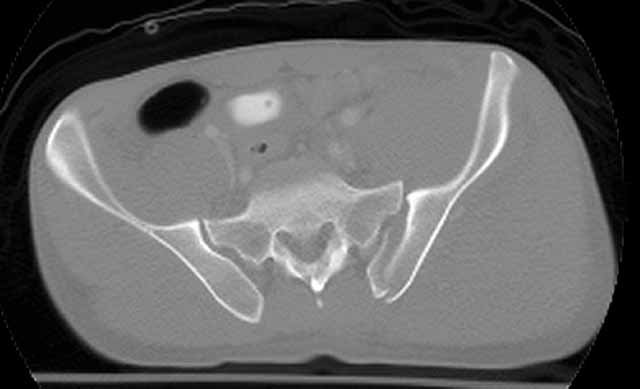

We initially did an ORIF of the femoral neck and then the head using a modified Smith-Petersen exposure with the patient positioned supine. The femoral head fracture fragment was without soft tissue attachments and removed temporarily. The ligamentum teres had been disrupted from its femoral head attachment so it was debrided. The dislocated head-neck fragment was then rotated out of the posterior impaction area, manipulated into the acetabulum preserving it s limited capsular remnants, rotated it to fit the neck, and then stabilized with screws inserted through stab wounds and guided by fluoroscopy. Then we reduced and used small screws to hold the previously removed femoral head fracture fragment.

For a variety of reasons we stopped at that, placed him in traction, and repeated his films and CT.

Two days later we returned to the OR and tried a closed manipulative reduction of the SI joint-iliac fracture but it failed, so we used the lateral (iliac) window of an ilioinguinal exposure to clean, reduce, and clamp the SI joint. We stabilized it with an iliosacral screw and closed.

Under the same anesthesia, we used a prone K-L exposure to reduce the impaction fragment, fold down the posterior wall, and hold it with a plate.

Here are the films....the staple lines mark his incisions.

CT SI Joint

We'll use ectopic bone prophylaxis and protect his weight bearing.